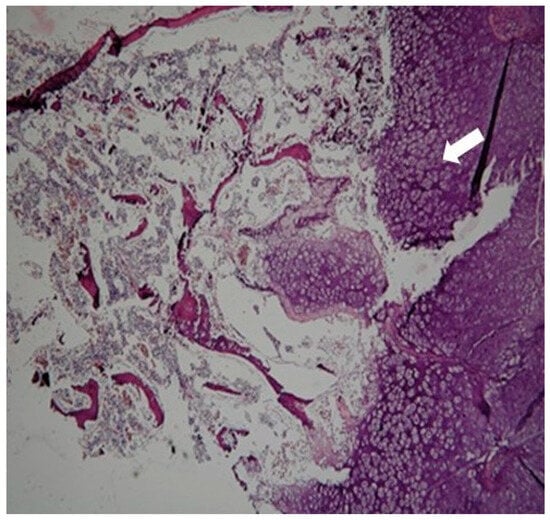

2. Case Presentation